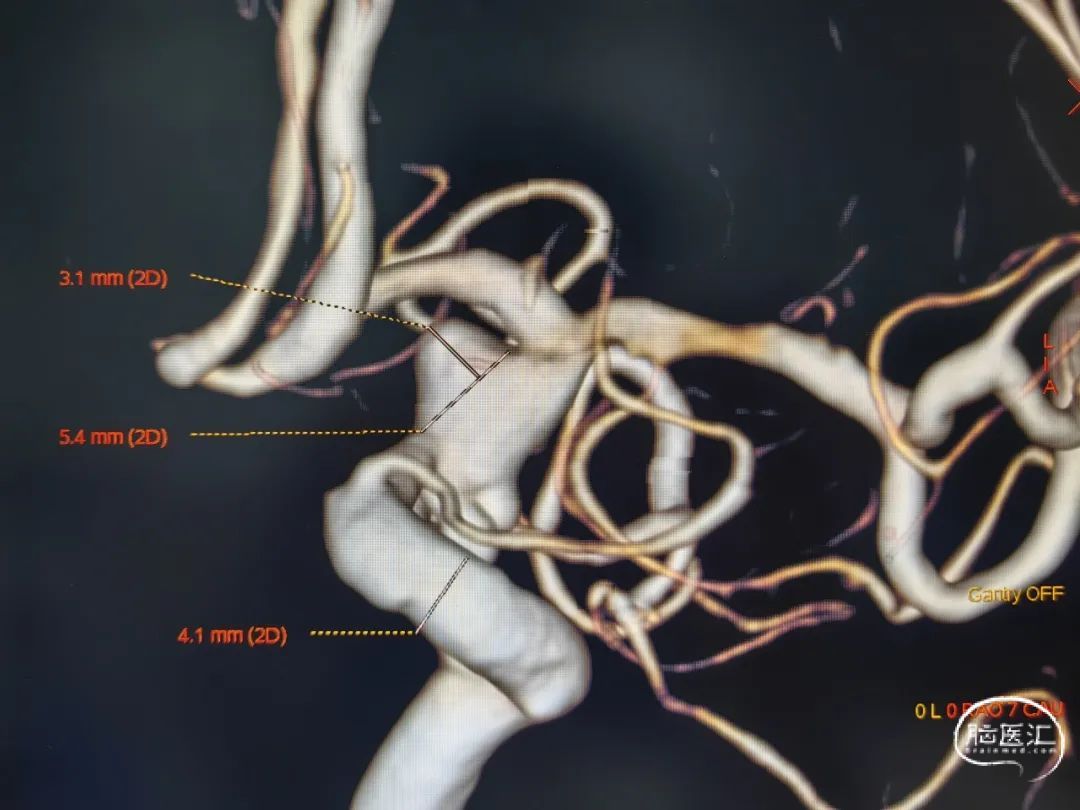

急诊DSA:

左颈内动脉后交通段多发动脉瘤

蛛网膜下腔出血(Hunt-Hess:2级)

交通段颈内动脉膨大,形态不规则且多发动脉瘤,故选择密网支架辅助弹簧圈栓塞。